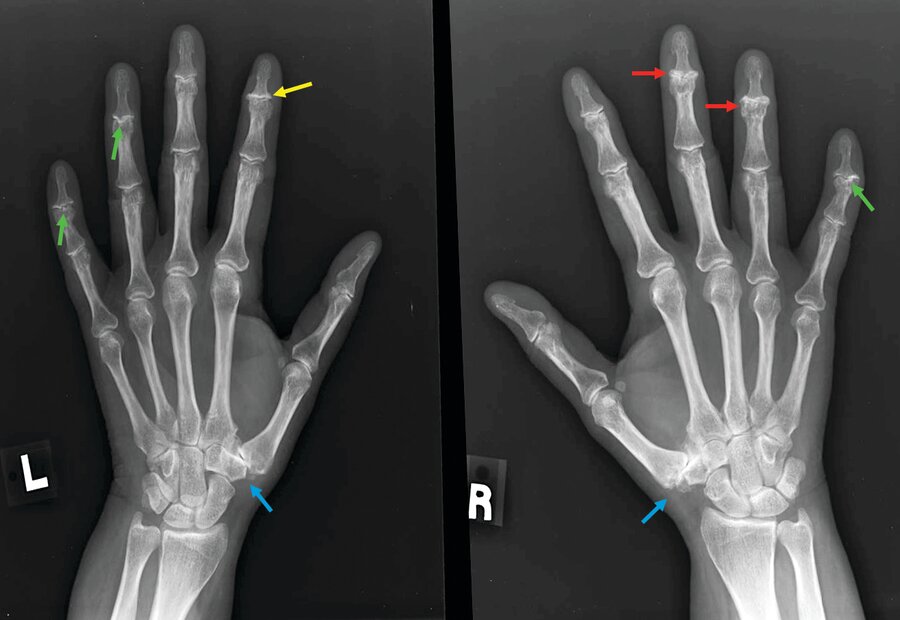

XR of hands show erosions in the DIP and PIP joints centrally and at joint margins. Asymmetric osteophytes are noted at the PIP and DIP joints bilaterally, with subchondral cyst formation. What's the diagnosis?

Erosive osteoarthritis mostly affects the distal interphalangeal and proximal interphalangeal joints, is characterized by erythema and swelling, is more common in women and is associated with conditions such as obesity, hypertension, and hyperlipidemia